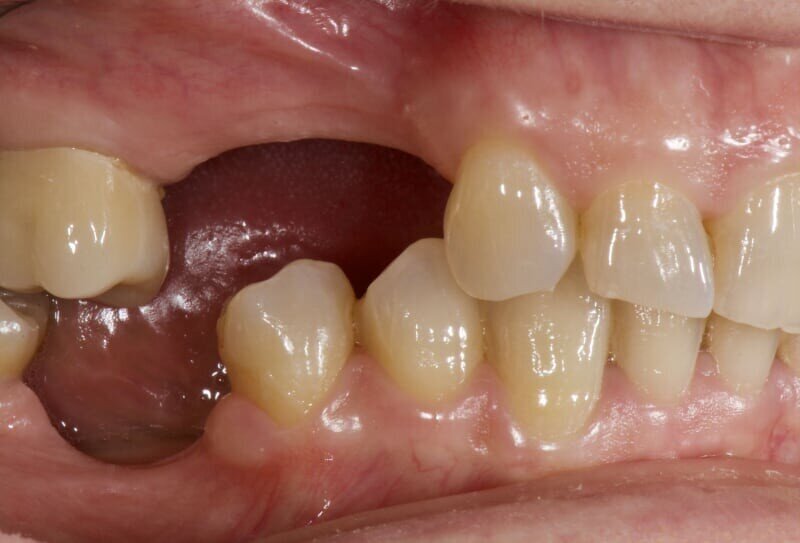

In questo case report è stata selezionata una paziente di sesso femminile, S.P. (54), non fumatrice, con buona igiene orale e con anamnesi negativa all’assunzione di farmaci, ad allergie, disturbi metabolici e patologie sistemiche (Figg. 1-3). È stata proposta una tecnica di rialzo del seno mascellare eseguita mediante strumenti piezoelettrici (Piezosurgery®, Mectron, Genova, Italy) (Figg. 9, 10, 13).

La severità del riassorbimento, e quindi dell’atrofia, è correlata alla durata dell’edentulismo. Gli individui edentuli da lunga data, difficilmente presenteranno una quantità di osso sufficiente all’inserimento di impianti senza nessuna manovra rigenerativa, in particolare nel settore posteriore4. Il fattore limitante per l’inserimento degli impianti non è tanto la larghezza quanto l’altezza della cresta ossea residua, compresa tra la cresta alveolare e il pavimento del seno mascellare5. Si può osservare, inoltre, che la riduzione del processo alveolare può avvenire anche in seguito a processi patologici correlati al dente, come forme di malattia parodontale o lesioni periapicali. Inoltre, da non sottovalutare, anche il ruolo delle lesioni traumatiche. Per poter attuare un piano di trattamento implanto-protesico corretto è quindi indispensabile classificare il grado di riassorbimento osseo al fine di effettuare uno studio pre-operatorio di ogni caso ed un conseguente piano di trattamento6.